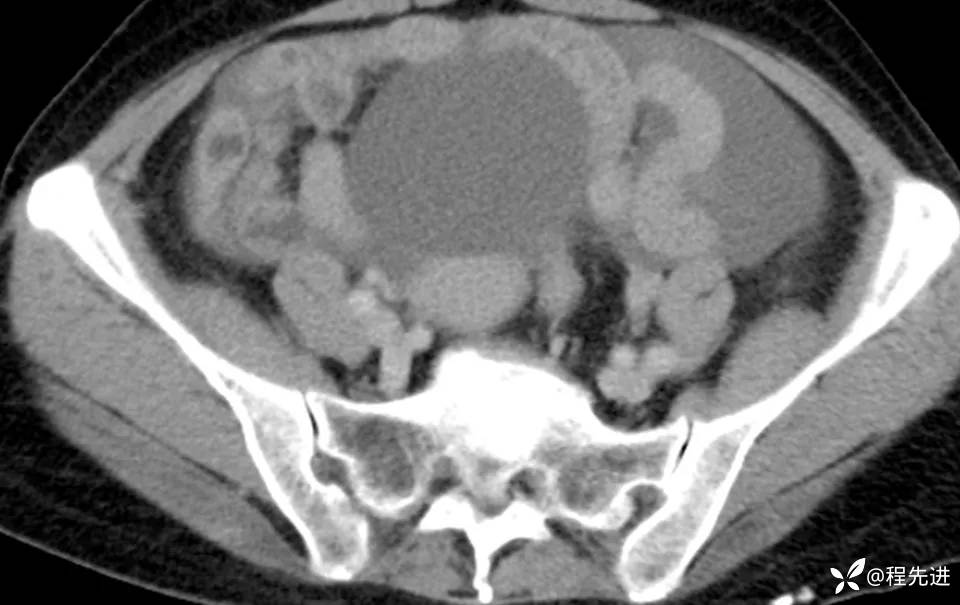

患者性别:女

患者年龄:56岁

简要病史:腹胀伴劳累性胸闷1月

肿标:CA125: 546.99U/ml;CA199: 269.9 U/ml,余未见异常

CT平扫+增强: